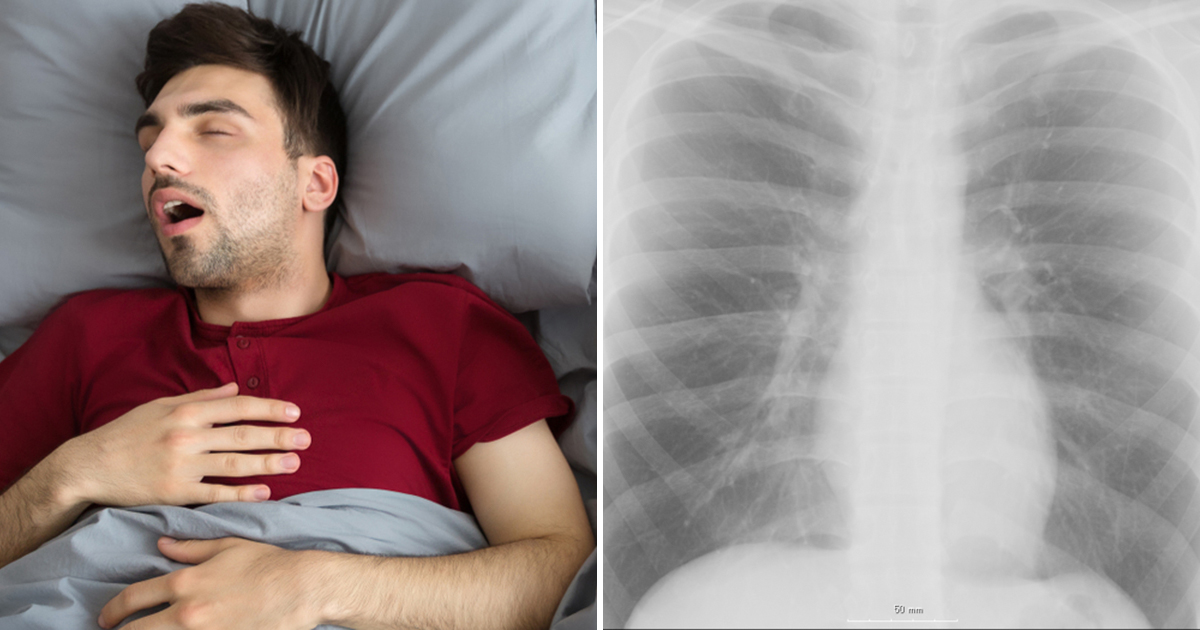

מחקר חדש פורסם בחודש דצמבר האחרון, והוא מראה שזה עלול להיות מזיק לבריאות לישון לצד מישהו שנוחר בחוזקה כל הלילה.

לפי הסטטיסטיקה 40% מהגברים נוחרים בלילה, לעומת 24% אחוזים בלבד אצל הנשים. משמעות המספרים הללו היא שהבריאות של הנשים בסכנה.

מומחים בארגון לחקר השינה באילינוי, ארצות הברית, ערכו מחקר על אנשים נוחרים ועל ההשלכות שיש לנחירות הללו על אלו שצריכים לישון לידם.

במחקר, שפורסם כאן, החוקרים גילו שהנחירות של בן/בת הזוג מפריעות כל כך לשינה שהן מהוות סכנה בריאותית.

המחקר הראה ש 14% מהמשתתפים נוחרים בעוצמת ווליום שמגיע עד 53 דציבלים.

"עוצמת רעש של 53 דציבלים עלולה לגרום לבעיות לב באוכלוסיות שחשופות לבעיות מן הסוג הזה", רשום במחקר.

חשיפה קבועה לנחירות בזמן שאתם מנסים לישון יכולה לגרום ללחץ רב על הלב, וכתוצאה מכך לגרום לבעיות לב שונות.

הכליות, המוח, והעיניים יכולים להיות מושפעים מכך גם כן.